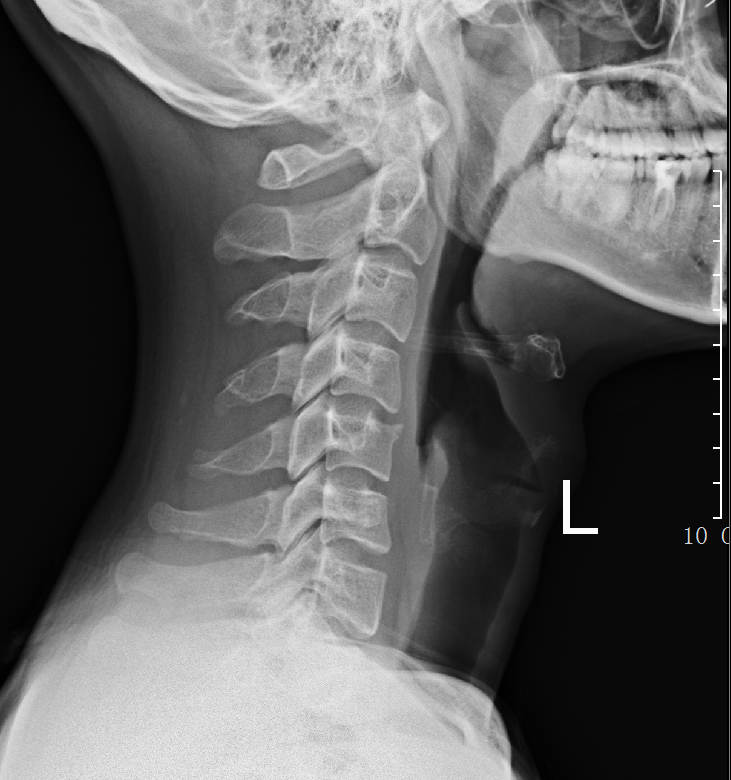

以下是小陳的頸椎側(cè)位片

于是,小陳來到惠州市第三人民醫(yī)院骨科醫(yī)學(xué)中心門診就診。骨科無創(chuàng)治療中心的龔輝醫(yī)生在看了他的頸椎片子后對(duì)他說:“小伙子,你是一個(gè)典型的直男??!”

龔醫(yī)生解釋:“直男”并非那個(gè)網(wǎng)絡(luò)語,而是指患者頸椎的生理弧度反弓,又稱生理曲度變直,有頭暈現(xiàn)象,原因大多由于慢性勞損,導(dǎo)致頸椎部位的骨骼增生、退變,生理曲度消失,出現(xiàn)變直的情況。這會(huì)對(duì)雙側(cè)椎動(dòng)脈產(chǎn)生壓迫,影響患者的腦部供血,進(jìn)而腦部供血不足,出現(xiàn)頭暈、惡心、嘔吐等臨床表現(xiàn)。這個(gè)病跟性別無關(guān),假如女性有類似的癥狀,也可以稱是一位“直女”!

通過X線片上的頸椎顯像:沿此曲度走行,在各個(gè)頸椎椎體后緣都有形成的連續(xù) 、光滑的弧形曲線,醫(yī)學(xué)上稱之為頸椎曲度。頸椎生理曲度的存在,能增加頸椎的彈性,減輕和緩沖重力的震蕩,防止對(duì)脊髓和大腦的損傷。